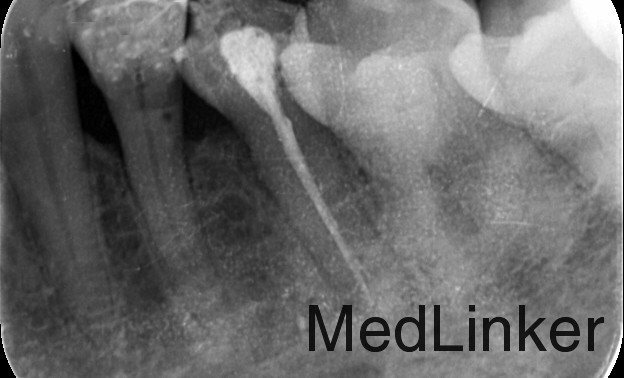

检查: 35合面见牙色充填物,探边缘密合,叩痛(+),松动I度,牙龈轻度红肿。 X线示:35根管内见致密根充影像,牙根根上、中1/3交界处连续性中断。

诊断:35根折 治疗计划:35拔除 治疗:35局部消毒,碧兰麻局部麻醉下,挺松拔除,搔刮牙槽窝,复位,局部压迫止血。常规拔牙后医嘱。 建议:修复科制定全口缺失牙修复计划